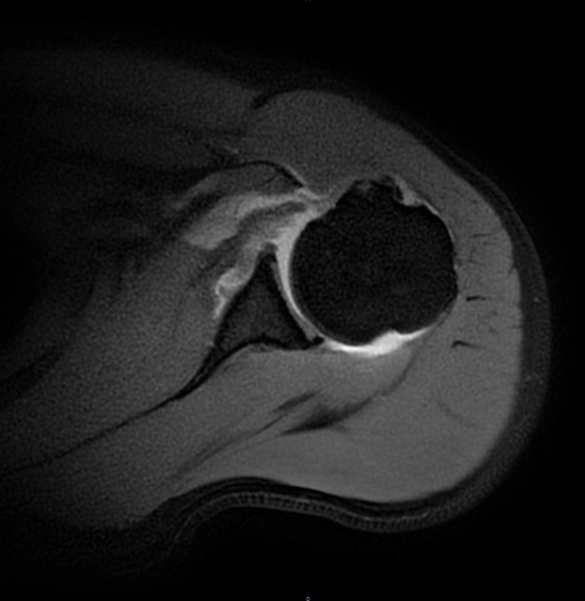

张华主任经过细致查体,怀疑这是肩胛下肌损伤。进一步的磁共振检查印证了判断,李先生肩胛下肌的止点位置撕裂了。“掰手腕时瞬间的力量不平衡,就像猛拉一根绷紧的绳子,很容易导致肩胛下肌急性撕裂。”张主任解释,李先生的这种损伤若不及时修补,肌肉会慢慢萎缩,不仅影响肩关节力量,还可能导致长期功能障碍。